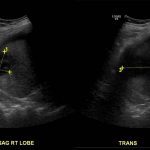

- Heterogeneous hypoechoic lesion in the periphery of the right hepatic lobe measuring up to 5.5 cm without internal vascularity

- Hepatomegaly with coarsened hepatic parenchymal echotexture

- Small volume, heterogeneous appearing perihepatic fluid

Heterogeneous hypoechoic lesion in the periphery of the right hepatic lobe measuring up to 5.5 cm without internal vascularity, concerning for an abscess. Adjacent small volume complex ascites raises concern for intraperitoneal rupture.

Hepatomegaly with coarsened hepatic parenchymal echotexture, concerning for cirrhosis.

- Depending on the internal contents, abscesses may appear predominantly hyper- or hypoechoic and may mimic solid liver masses